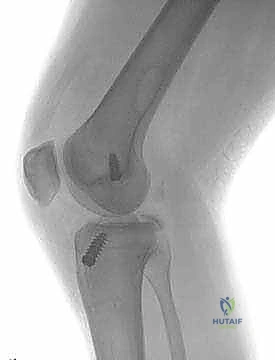

- الأشعة السينية (X-rays): لاستبعاد وجود كسور عظمية، خاصة كسور الانقلاع (Avulsion fractures) حيث ينفصل الرباط حاملاً معه قطعة من العظم.

- الأشعة السينية مع الضغط (Stress Radiographs): يستخدمها الدكتور هطيف أحياناً لقياس مقدار الإزاحة الخلفية بالملليمترات بدقة متناهية، مما يساعد في اتخاذ قرار الجراحة.

5. الكسور الانقلاعية (Avulsion Fractures): حيث يحتاج العظم المنفصل إلى تثبيت فوري بالمسامير.